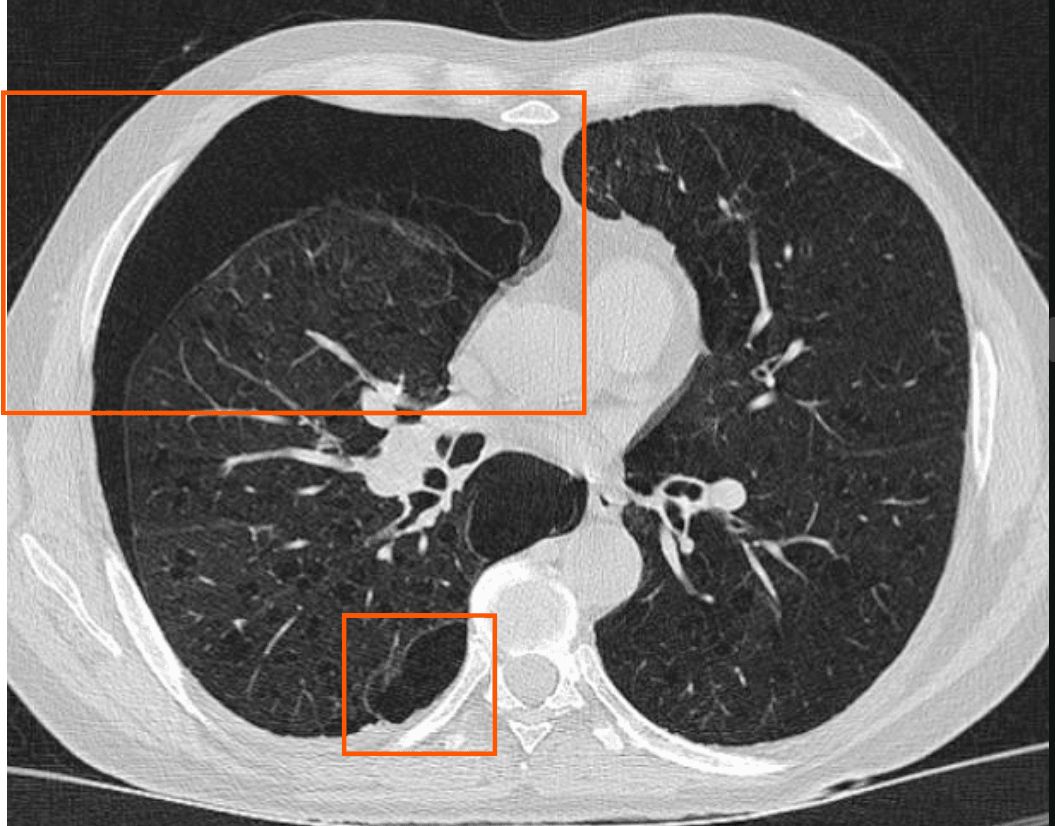

CT 소견

작은 기흉까지 감별 가능하며, 폐포 손상 및 기도 이상을 보다 정밀하게 평가.

| CT 소견 |

| 🔵 공기 음영 증가: 흉막강 내 공기가 명확하게 보이며, 폐 실질과 구분됨. |

| 🔵 늑막 두께 변화: 기흉으로 인해 내측 흉막과 외측 흉막 사이 간격이 증가. |

| 🔵 종격동 변위: 긴장성 기흉의 경우 압력 증가로 인해 심장 및 기관이 반대쪽으로 밀려남. |

Cuete D, Secondary spontaneous pneumothorax.

영상 소견상 특징

- Right Pneumothorax

- Signs of bullous emphysema of apical predominance